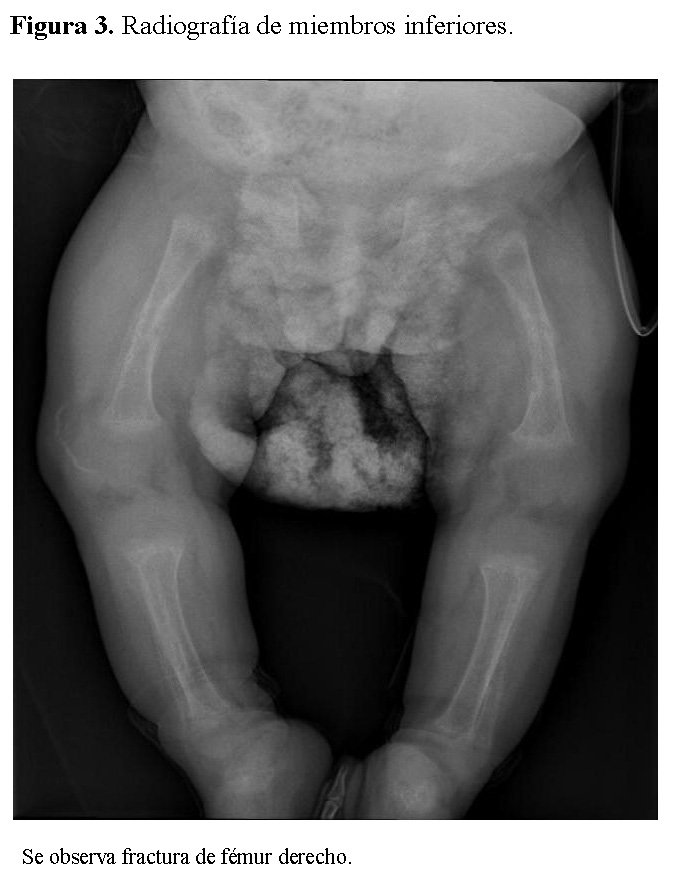

Chest radiography showed bilateral heterogeneous parenchymal infiltrates, pleural thickening, and right-sided rib fractures in the consolidation phase (Figure 1). Radiographs of long bones revealed severe osteopenia, periosteal reaction, and multiple pathological fractures, including the right and left humerus, right ulna, and right femur (Figures 2 and 3).

Figure 1.